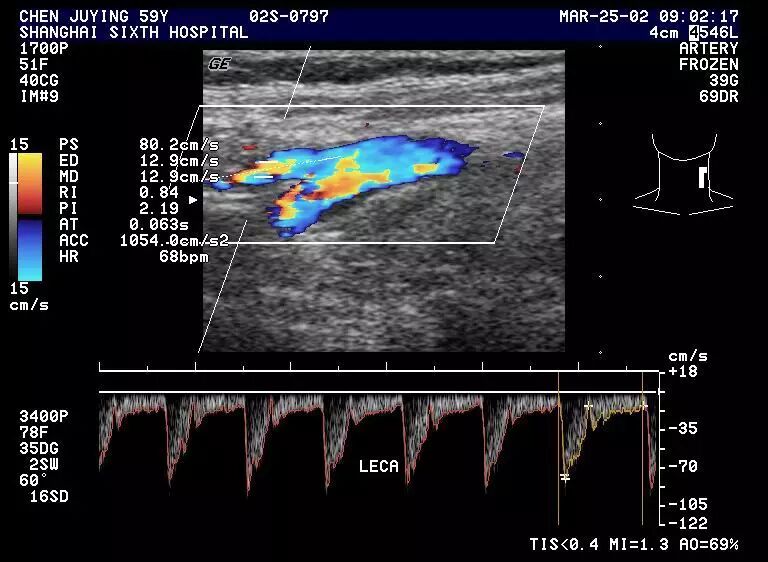

(3) 正常颈外动脉,显示高阻型血流频谱,收缩期流速迅速升高,舒张期下降也快呈尖蜂状,舒张期仅少量低速血流。

1.3 正常颈外动脉频谱